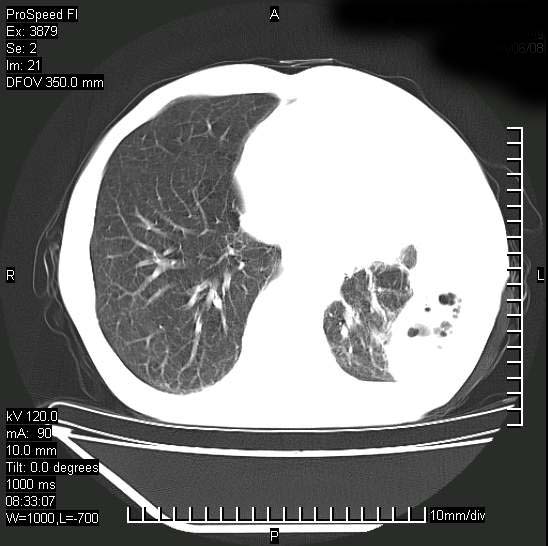

以下是引用37度在2008-6-6 11:20:00的发言:[br]1.包裹性积液,多考虑结核性;[br]2.穿刺术后改变。

以下是引用312nanyang在2008-6-6 15:12:00的发言:[br]基本支持楼主意见[br]疑问?左下肺支气管旁的软组织(16层)密度怎么解释?淋巴结还是斜裂胸膜增厚所致?能否增强进一步检查